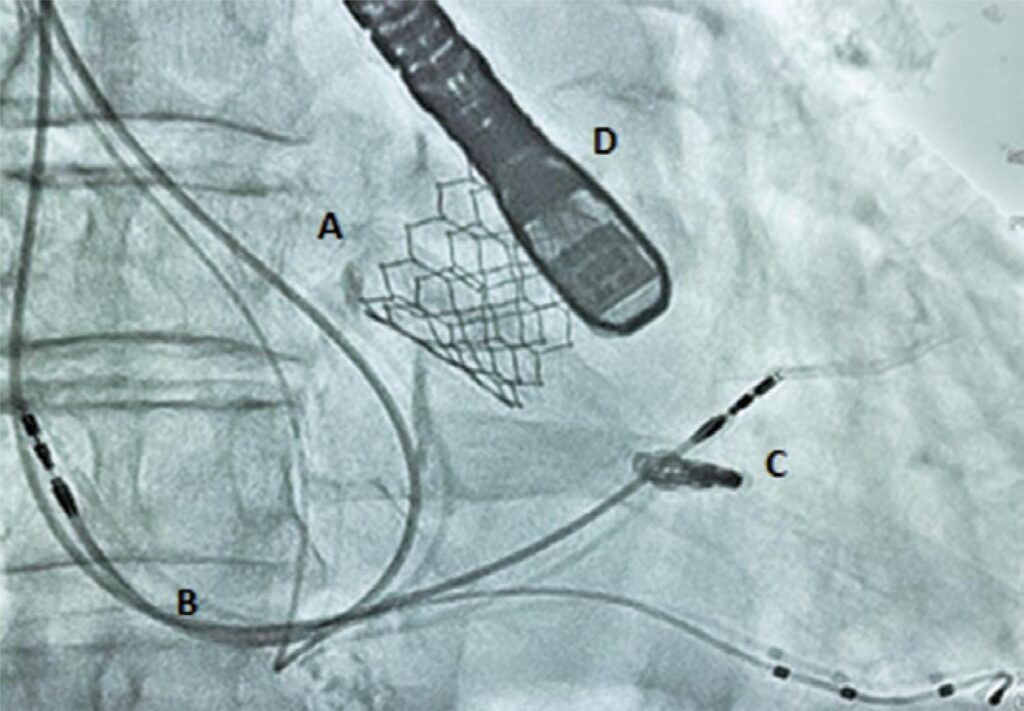

Reparo valvar percutâneo borda a borda da insuficiência mitral após implante transcateter de válvula aórtica

A insuficiência mitral moderada a grave é observada em 17 a 35% dos pacientes submetidos a implante transcateter de válvula aórtica. Estudo que reporta a insuficiência mitral pós-realização de implante transcateter de válvula aórtica por estenose aórtica demonstra que 50% dos pacientes com refluxo moderado a grave apresentaram melhora da regurgitação, e 8,7% evidenciam piora do quadro. Nesses pacientes com piora, houve aumento da mortalidade. Essa progressão sugere que condutas convencionais, baseadas em otimização medicamentosa, podem não ser capazes de prevenir quadros negativos. Relatamos um caso sobre a evolução da insuficiência mitral após implante transcateter de válvula aórtica e o uso do MitraClip® como alternativa de tratamento e benefícios.